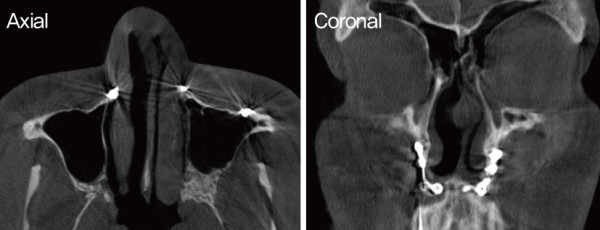

![]()

수술 전 CT. 비밸브 협착을 보였다. 비익연골의 내전과 비중격 미단 변형으로

인한 좌측 비밸브 협착이 확인되었다. 상악수술 후 삽입된 핀이 비골 바닥

부분에 산재되어 있다.

이러한 소견은 이전 양악수술에 의한 결과일 가능성이 있다. 또한 비익연골의 내전과 비중격 미단부의 변형으로 인한

좌측 비밸브 협착이 관찰되었다.